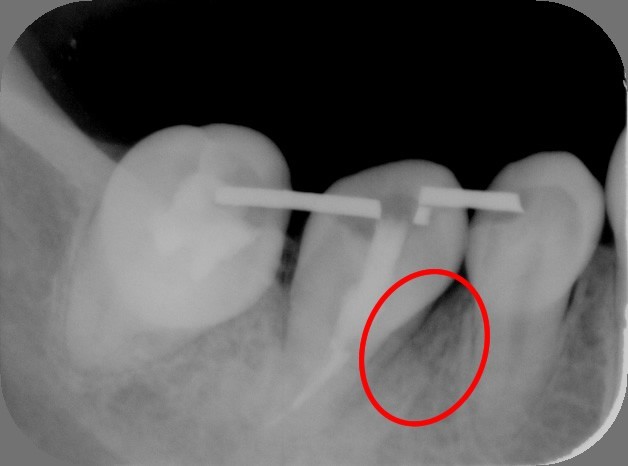

2.抜歯直後